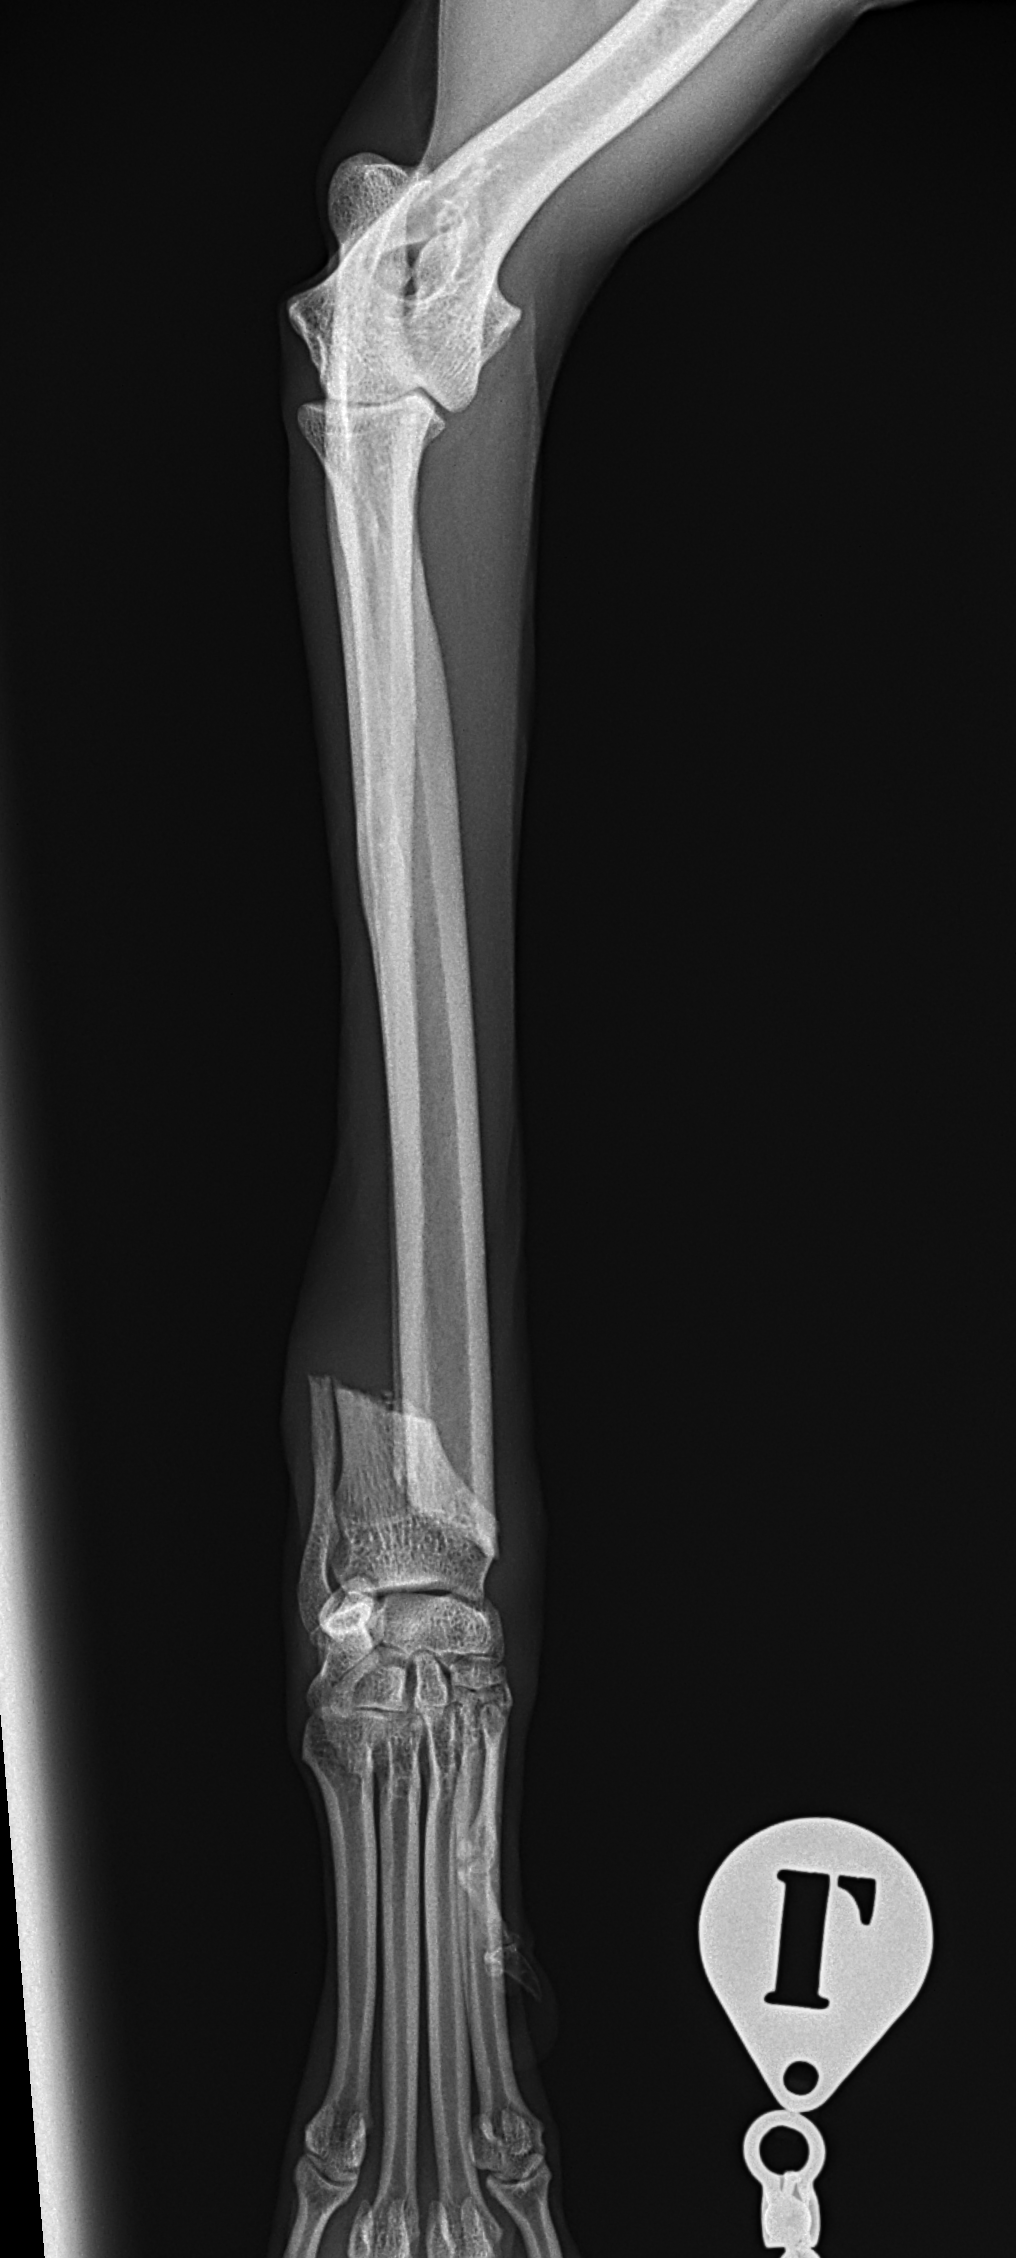

橈骨固定術 #239

イタリアングレーハウンドがジャンプした後から跛行しているとの事。2.4 Locking Plateで固定術を行いました。しばらくはインプラントにロードベアリングしているため骨がロードシェアできるまでは初期固定強度を担保するために外固定の併用を行います。